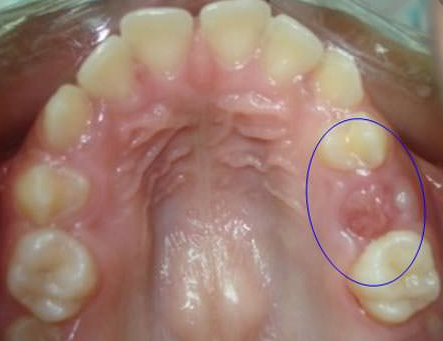

- Pérdida prematura de dientes de leche: si los dientes de leche se caen antes de tiempo y no se hace ningún tratamiento odontológico con un mantenedor de espacios (aparatología), tal como lo mencionamos en nuestro artículo ¿Por qué cuidar los dientes de leche si se van a caer?, los dientes de leche adyacentes pueden ocupar el espacio del diente perdido, tal como se muestra a continuación:

*Espacio por pérdida prematura de dientes de leche que debe ser conservado por un mantenedor de espacios, tomada de https://www.ortodoncia.ws/publicaciones/2009/art-17/